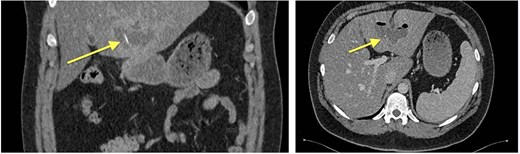

Repeat CT (05.05.2024) demonstrated the wire had migrated, now traversing the posterior gastric wall into the mesentery near the hepatic flexure. New gas collections in the Morrison pouch and right subdiaphragmatic space were noted [11].

Given persistent pain and fever, a second-look laparoscopy was undertaken. Access to the lesser sac via the gastrocolic ligament revealed the metallic wire (Fig. 2), embedded near the pyloric region. It was successfully extracted without mucosal rupture or abscess formation.